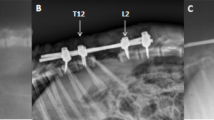

Dogs were allocated to four groups. Group A (control) underwent laminectomy of T7 without shortening the spinal column. Groups B, C and D had 1/3, 1/2, and 2/3 of T7 resected, respectively, followed by spinal shortening. Somatosensory evoked potential (SSEP) and hind-limb function were recorded periodically for 14 days after operation. Spinal cord blood flow (SCBF) and BSCB were detected at the acute phase of shortening. Microglia/macrophage reactions and iNOS activity were observed by immunohistochemistry.

Shortening of 1/3 of a vertebral height caused no significant changes in SSEP and hind-limb function after operation, whereas shortening of 1/2 of the height caused SSEP abnormality and paraparesis, and severe neurologic deficit of hind-limb was observed when the shortening reached 2/3 of the height. SCBF increased temporarily and showed a trend of recovery when the shortening was within 1/2 of a vertebral segment height. When it reached 1/2 or 2/3 of the height, SCBF at 6 h post-operation was 86.33% or 74.95% of the baseline, and an increasing BSCB permeability was observed. In the subsequent 7 days, obvious activation of macrophage and increased number of iNOS-positive cells were observed.

It is safe to shorten the spinal cord within 1/3 of a vertebral height in middle thoracic spine under two-segment laminectomy in canine. The BSCB disruption, macrophage activation, and increased iNOS activity were observed in the acute phase of the injury.